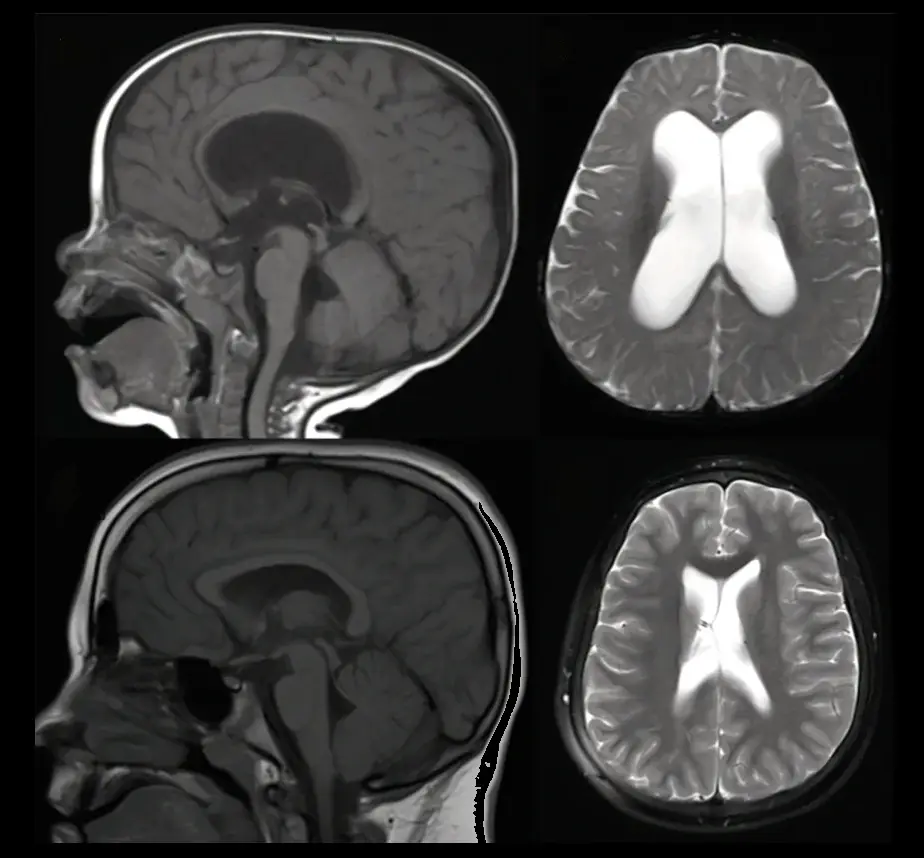

A hidrocefalia é uma condição neurológica em que há acúmulo excessivo de líquido cefalorraquidiano (LCR) dentro dos ventrículos cerebrais.

Esse acúmulo provoca aumento da pressão intracraniana e pode causar sintomas neurológicos importantes.

O diagnóstico da hidrocefalia é realizado por meio de avaliação clínica e exames de imagem, como ultrassonografia transfontanelar (em bebês), tomografia computadorizada e ressonância magnética.